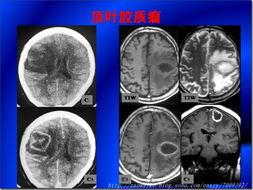

1. CT扫描下的脑瘤

CT扫描是诊断脑瘤的重要手段之一。在CT扫描的照片中,我们可以看到脑瘤的轮廓,以及它对周围组织的影响。这些照片,就像是一扇窗户,让我们得以窥见脑瘤的真面目。

2. MRI下的脑瘤

MRI(磁共振成像)是另一种常用的脑瘤诊断方法。与CT扫描相比,MRI可以更清晰地显示脑瘤的内部结构。在MRI的照片中,脑瘤的颜色和形状更加明显,让人触目惊心。